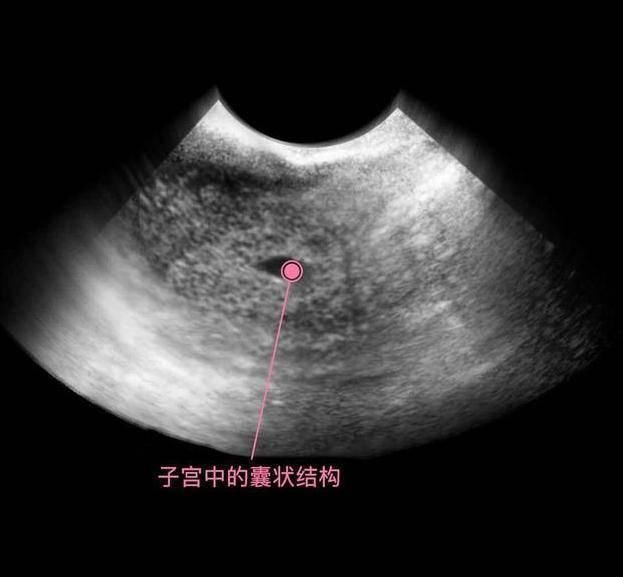

上图可见子宫中的囊状结构,胎儿由两层的组织构成胚胎,所有的器官和组织都是有这些组织发育而成,胚胎羊膜囊的空腔中,开始有羊水积聚,为将来包裹和保护胎儿做准备。